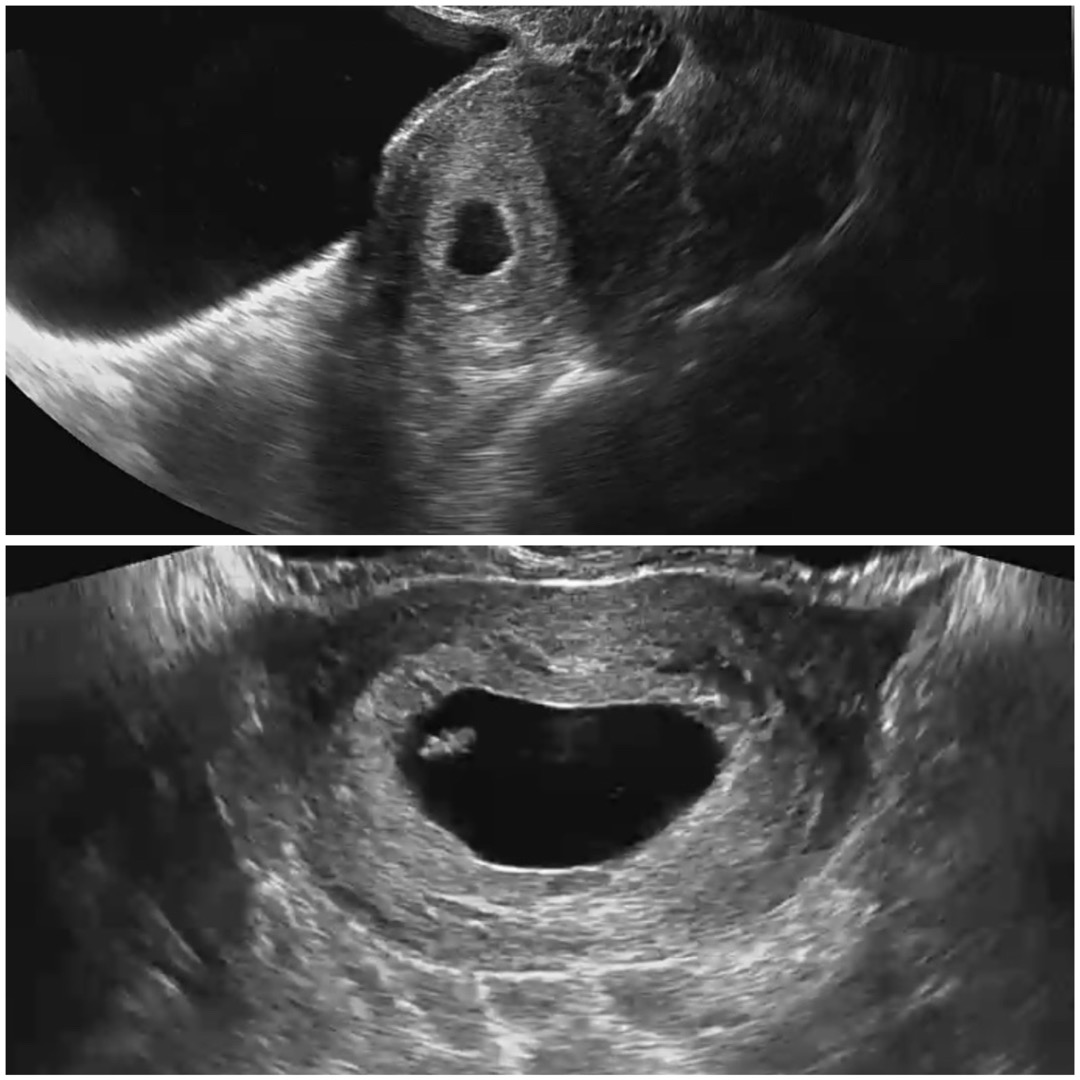

위에 사진이 5주 6일째 아기집 크기이구 아래 사진이 오늘 가서 찍어본 7주 0일째 아기집이랑 아기 사진인데 불과 약 10일지났는데 아기집이 12.3mm 크기였었는데 오늘 가보니까 아기가 8mm크기가 되어있고 집은 무슨 엄청 크게 지어졌네요ㅋㅋㅋㅋㅋ 의사쌤도 집이 크게 잘 지어졌다면서 웃으시더라고요ㅋㅋㅋㅋㅋㅋ 10일만에 이런 변화가 있다는게 엄청 신기해요 다들 이러셨나요~?ㅎㅎ